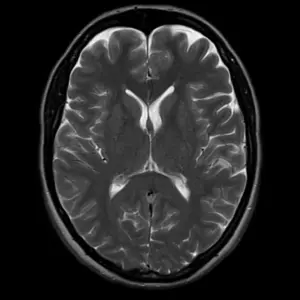

Ο τομογράφος χρησιμοποιώντας το φαινόμενο του μαγνητικού συντονισμού των μορίων νερού και σύγχρονα υπολογιστικά συστήματα δημιουργεί εικόνες εγκάρσιες, επιμήκεις και 3D του ανθρώπινου σώματος.

Σε αυτή την εξέταση απεικονίζεται με τη χρήση ή χωρίς σκιαγραφικού μέσου το παρέγχυμα ,τα οστά και όλες οι δομές του εγκεφάλου των νεύρων και του νωτιαίου μυελού διαγιγνώσκοντας παθήσεις όπως υδροκεφαλία, ριζίτιδες, όγκους κ.α.

Απεικονίζεται η νευρωνική δραστηριότητα του εγκεφάλου μέσω των αιμοδυναμικών αντιδράσεων αυτού. Με αυτό τον τρόπο καθώς και με την δεμιτογραφία (DIT) ελέγχονται κέντρα που ελέγχουν την ομιλία, την μνήμη και την κίνηση γι’αυτό πολλές φορές ο ασθενής συμμετέχει στην εξέταση ακολουθώντας οδηγίες (π.χ. ανασ;hκωση χεριού κ.α.)

Eλέγχεται η μεταβολική δραστηριότητα του εγκεφάλου. Αποτελεί σημαντικό εργαλείο για όγκους, απομυελυνωτικές εστίες κ.α.)